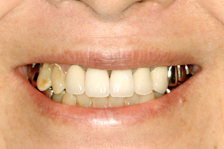

右の前歯が一本ありません。

最初の仮歯の状態です。

症例2

前歯の場合笑った時の歯の

見え方、歯茎の見え方も注意してインプラントの位置を考え

なければなりません。

他の残っているご自分の歯に

形を合わせないと審美的に

満足はえられません。